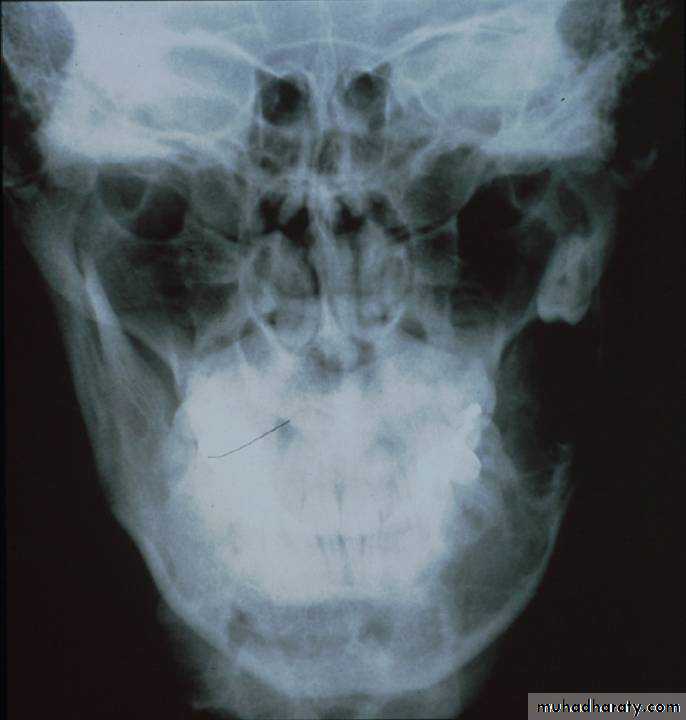

Radiographical appearance• Usually well-circumscribed;

• Multilocular Radiolucency.• (Honeycomb) or (soap- bubble) appearance.

• Recently diagnosed by:

• Computed tomography (CT) scan.

• Magnetic resonance imaging (MRI).